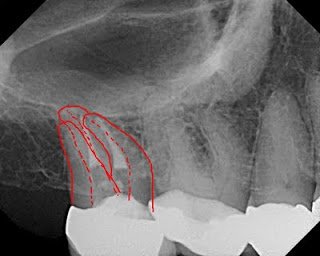

In addition to the above two radiographs, I also examined a bitewing and two traditional film radiographs which I chose not to include here. One thing that stands out is that the crown margin is placed on the buildup, not an ideal situation. You can see only two canals treated and an in tact PDL. The orifices of the canals are clearly overenlargedand the obturation does not appear to follow the root anatomy.

Drawn below is what I drew for the patient, predicting the true root and canal anatomy of the tooth and showing where I speculated there to be an untreated distal buccal canal.